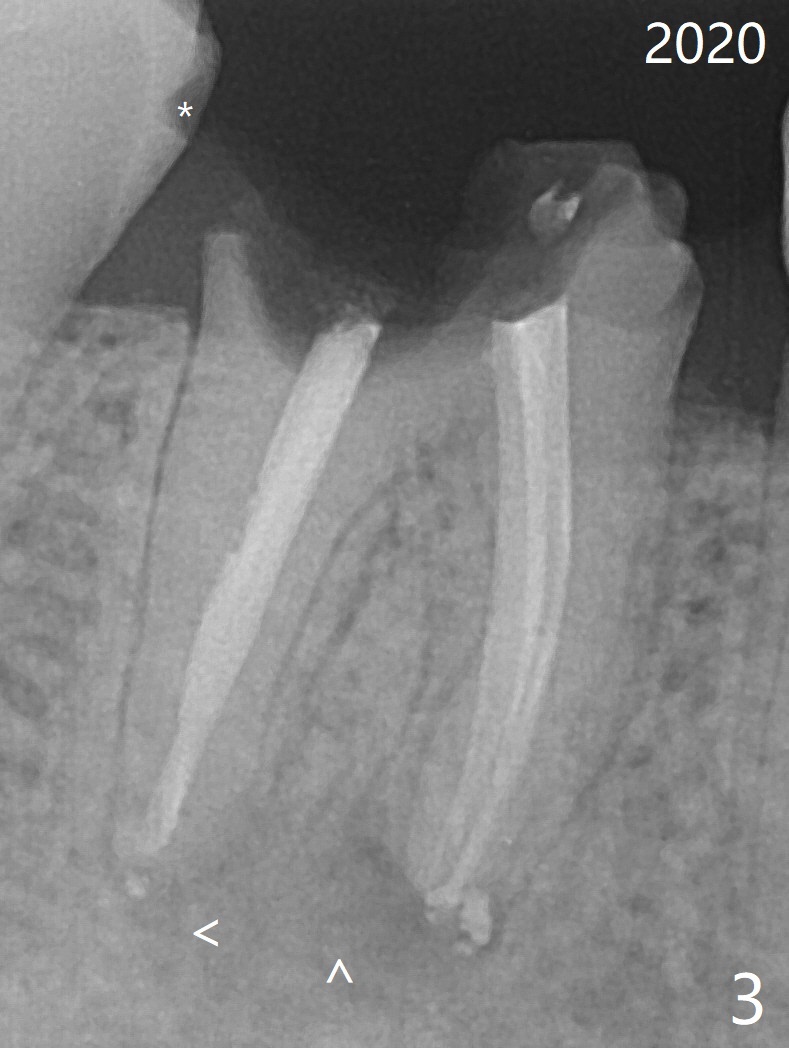

55岁女特别害怕牙科治疗,6年前右下6根分叉以及根尖阴影(图一),根管治疗后3年(图二(阴影消失))才回来做牙冠,现在牙冠因为继发性龋齿而脱落(图三(根尖阴影重现)),病人同意导板即刻种植(图四)。用外科手机去除中隔冠方牙根,完成钻洞后拔除牙根,放入植体。